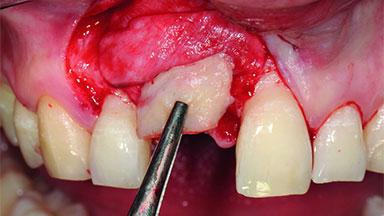

Replacement of a Compromised Upper Right Central Incisor: Hard- and Soft-tissue Augmentation, Late Placement of an RC Bone Level Implant

A 36-year-old male patient with a compromised maxillary central incisor was referred by his general dentist for consultation. The patient’s chief complaints were the gradual debonding of a temporary crown on the right central incisor and unsatisfactory esthetics due to an increasing diastema between the right central and lateral incisors. The patient reported a traumatic event some years previously, when a crown had been placed after root-canal treatment. The referring dentist wanted to provide a new crown restoration, but was concerned about the condition of the residual root. Anamnesis was negative for any other dental or periodontal pathology in the remaining dentition. The patient reported taking no medications: He was a smoker (10 to 15 cigs/day) and had realistic esthetic expectations.